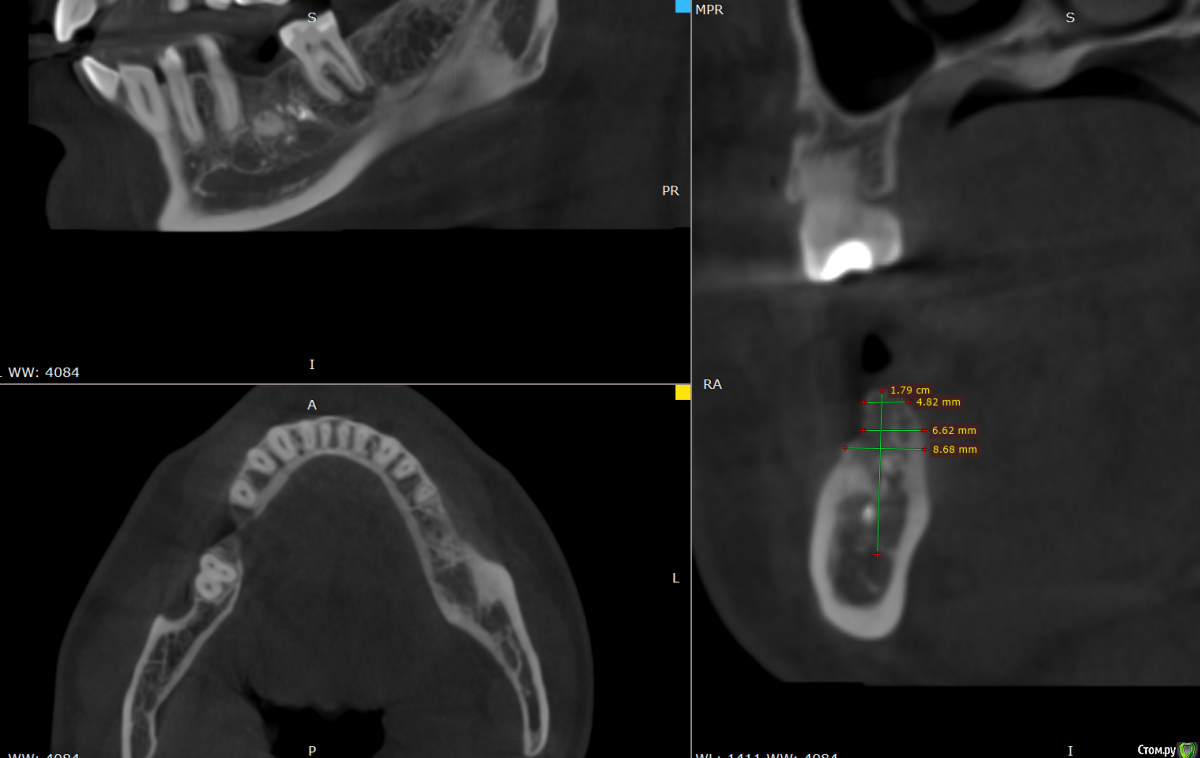

Valerkaa Опубликовано 15 декабря, 2019 Автор Поделиться Опубликовано 15 декабря, 2019 Большое спасибо. Вот с размерами. №1 и №2 Ссылка на комментарий

___49___ Опубликовано 27 декабря, 2019 Поделиться Опубликовано 27 декабря, 2019 Большое спасибо. Вот с размерами. №1 и №2Кейс 1 - требуется удаление всех конкрементов в области будущей имплантации, на полное их извлечение при формировании ложа надеется не стоит. кейс 2 - требуется хирургическое лечение, скорее всего киста примерно как в этой теме http://forum.stom.ru/topic/37994-kista/ Ссылка на комментарий

Bier Опубликовано 30 декабря, 2019 Поделиться Опубликовано 30 декабря, 2019 Кейс номер 1Устанавливать с заглублением конический или TL имплантат. Без пластики, без "чистки" кости. Кейс номер2Ретенционная киста, ЛОР лечения не требует. Можно сдуть ее шприцем или удалить на операции. 2 Ссылка на комментарий